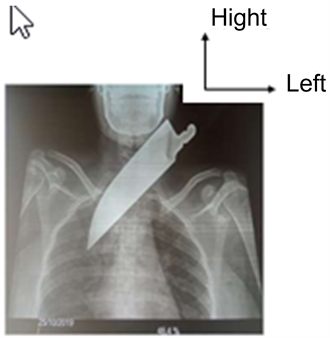

The standard radiography cervico-thoracic revealed a radio-opaque image oriented obliquely and directed latero-cervically towards the apex of the right lung without pneumothorax or pneumomediastinum (Figure 2).

Figure 2. Front view cervico-thoracic X-ray.

In the present study, the reason for consultation was the knife implanted in the neck. This is one of the main reasons for penetrating cervical wounds after attempted suicide [11] [20] [22]. Other reasons reported by the authors were hemoptysis and dyspnea [7] [23]. In the study, the time before admission to the emergency department of the hospital was approximately one (01) hour. This is similar to the duration noticed by Weale et al. in South Africa in 2019 [7]. Kaufeld et al. in Germany in 2016 had a shorter admission time of fifteen (15) minutes [24]. However, some authors have recorded longer delays. Sanju et al. in Toronto in Canada had recorded delays of four (04) days [13], Adeyi et al. in Nigeria had had cases arriving in consultation after twelve (12) hours to four (04) days after the suicide attempt [15]. There is a contrast between lesion severity and mortality [1] [25]. Among the psychotic disorders of young subjects, the risk of suicide is always present in a depressive phase [7] [20]. A prompt primary clinical examination should be performed, consisting of checking and treating disorders of the airways and blood circulation. It is not easy to make a decision about exploring the neck [5]. According to Alao et al. in New York in 2021, the local examination should very quickly appreciate any deformity and hematomas which can contribute to an imminent obstruction of the airways [26]. The local examination revealed the presence of a knife blade stuck in the neck with an entry hole located approximately one (01) cm above the sternal notch in the right paramedian. It was zone 1 according to the classification of Monson and Selata, which exposed cervico-thoracic vessels, the trachea, the right lobe of the thyroid gland, and the carotid artery [2] [26]. The diagnosis of a penetrating neck wound is clinical and relatively easy. It is a wound that has deeply penetrated the platysma muscle of the neck [5]. Above all, it poses a problem of lesion diagnosis and therapeutic attitude. Their potential seriousness makes them a concern for the ENT surgeon [1]. For Misiak et al. in Poland in 2016, the knife blade retained in the neck can at the same time play the role of local hemostasis [25]. The linear wound of the knife blade penetration site measured five (05) cm in the longitudinal axis (Figure 1), yet the depth was eleven (11) cm. Some authors thought that there is a weak correlation between the location of the external wound and the lesions of the internal structures [27]. These factors challenged the whole basis of the traditional zonal approach, according to which the majority of vital structures are located in the anterior triangle of the neck [28]. We adopted the non-zonal or selective approach to penetrating neck stab wounds, where the entire neck was assessed as a single entity. The results of the biological assessment showed a mild normocytic normochromic anemia and moderate thrombocytopenia, there were no coagulation difficulties during the operation. Biological assessment in the context of a penetrating neck wound is of interest for hemodynamic evaluation and preoperative assessment [5] [20]. In this study, cervico-thoracic radiography was performed on a hemodynamically stable patient. The authors recommend that before its realization, it is necessary to take into account the availability, the possibility of being carried out according to whether the patient is hemodynamically stable or not and the medico-legal aspect [7] [12] [21] [26].